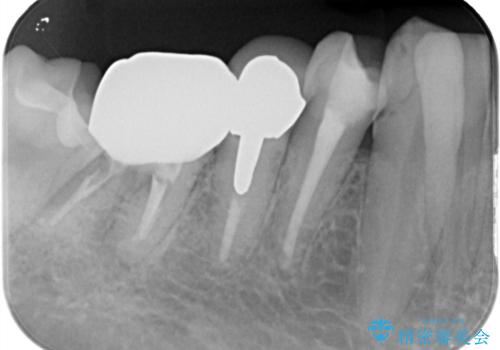

- フロスをしていたが歯と歯の間にはさまり、取れなくなったとのご相談にいらした患者様です。以前、他院で治療した部分に凹みがあり、その部分にフロスが残留しちぎれていました。このため、根本的に歯のかぶせ物・詰め物を新しくする必要があると判断いたしました。治療後はフロスでのケアもスムーズになり、良好な経過をたどっています。

一般的に、失活歯(根の治療をし、神経を取り除いてある歯)はそうでない歯と比較し、噛み合わせの力がかかりやすいといわれています。残存する歯質の量にもよりますが、歯の破折を防ぐためにクラウン(かぶせ物)を選択するケースが多いです。